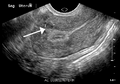

A very large (9 cm) fibroid of the uterus which is causing pelvic congestion syndrome as seen on ultrasound

A small uterine fibroid seen within the wall of the myometrium on a cross-sectional ultrasound view